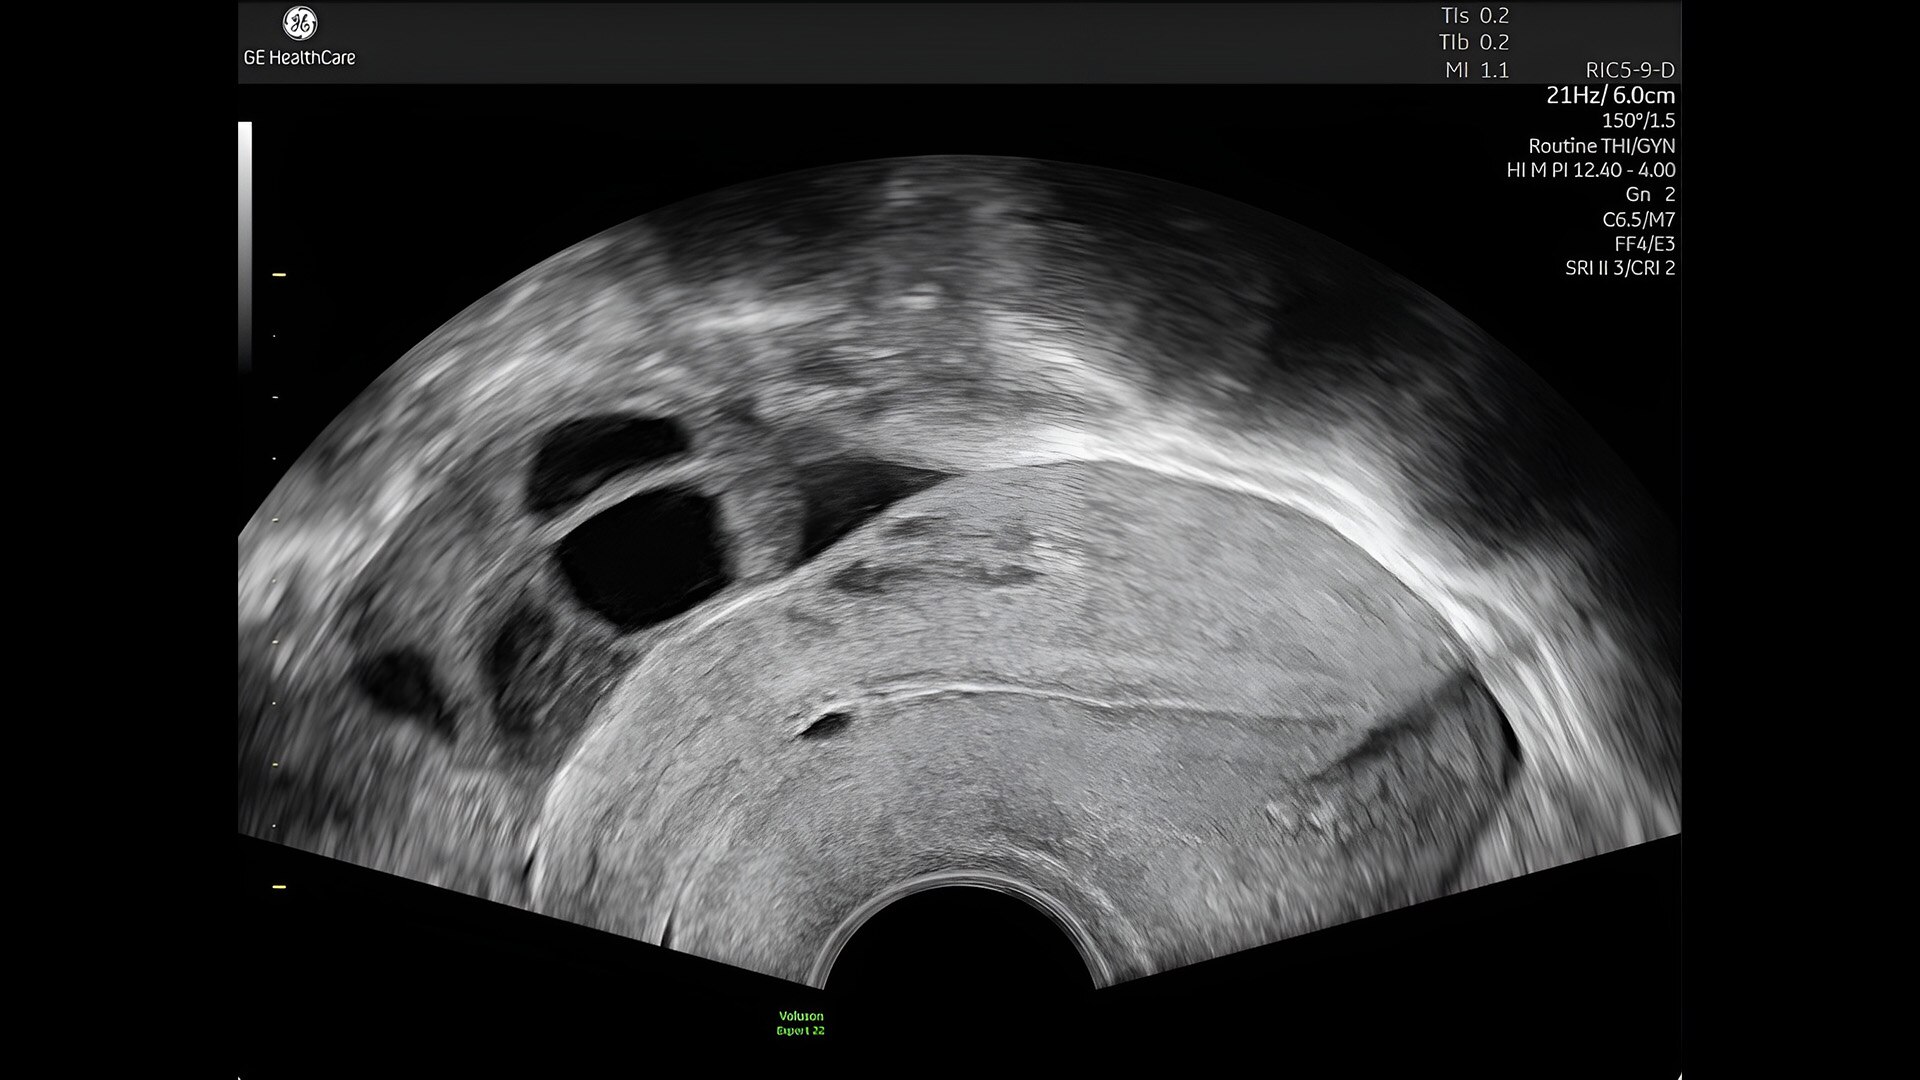

Complex cases come with enough uncertainty. That's why the Voluson Expert 22 is specifically designed for in-depth assessment of complicated anatomy — with pioneering first trimester, fetal cardiac, gynecological, and other pivotal technologies that focus on early detection and intervention.

First trimester exams

Perform detailed exams with high-resolution for early insights to fetal health